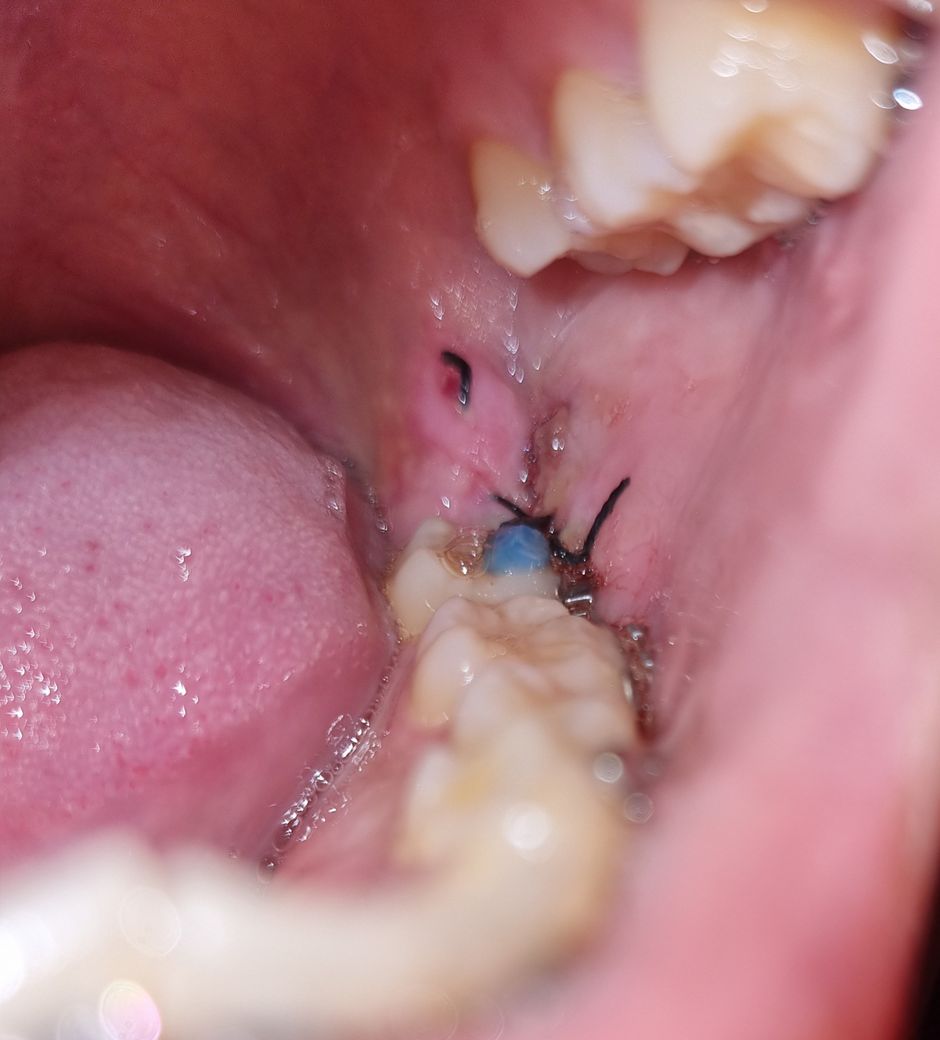

저번주 금요일(18일) 매복 사랑니를 발치했고 오늘(21일) 실밥이 끊어졌습니다. 당장 병원에 가야할까요?

첫번째 사진은 발치 첫날 사진이고, 두번째 사진은 방금 찍은 사진입니다. 사진 상 잘 보이진 않지만 실밥이 끊어진 자리에 하얀색 거품? 흉터? 같은게 짜글짜글 자리잡고 있습니다

• 2번 째 사진

하얀색은 육아조직이라고 하는 조직이며 회복과정에서 나타나는 정상조직입니다.

사진상에서는 문제될 사항이 보이지 않으나, 만약에라도 실밥이 만약 느슨해졌거나 풀어졌다하더라도 대체로 2차 치유과정에 의해서 정상적으로 회복되므로 걱정하실 필요없으며,

만일 실밥이 심각하게 터졌더라도 다시 봉합해봤자 이미 상피화과정이 진행되었기때문에 소용이 없습니다.

즉, 걱정하실 필요없으며 기다리면 저절로 치유됩니다.

사진만 봐서는 실밥이 풀러진것인지 명확하진 않습니다. 잇몸이 부어서 저렇게 보이는것일수도 있습니다.

또한 실밥이 풀러졌다해도, 굳이 치과를 당장 갈 필요는 없어보입니다.

방문하지 않으셔도 됩니다. 실밥으로 해당 부위를 묶어 놓고 상피가 접합되기를 기대하는 것인데 이미 어느정도 상피가 회복되었습니다. 따라서 방문하지 않아도 되고 간혹 발치 이후에 실밥이 빠지시는 분들도 있지만 상관 없습니다. 또한 말씀하신 거품 및 흉터는 정상적인 회복과정의 일환입니다.